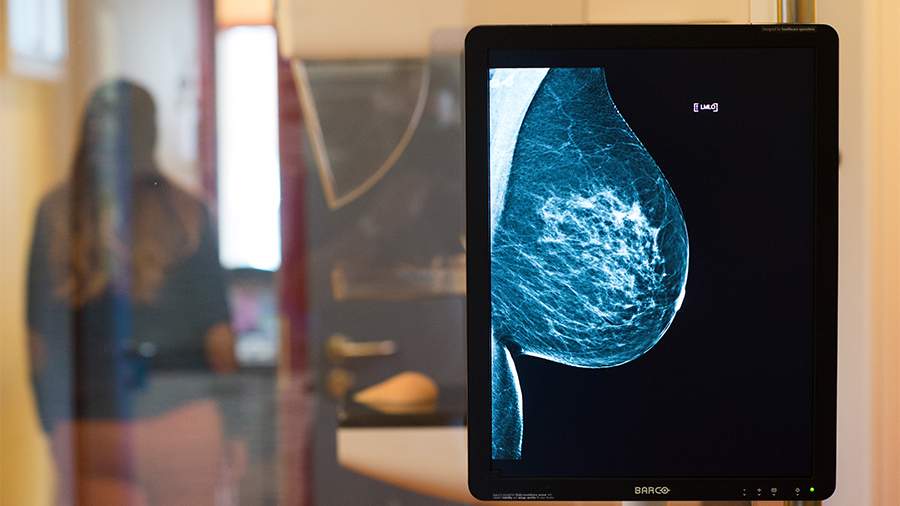

Врач Сулиманов: самоанализ раз в месяц поможет выявить рак груди на раннем этапе

Фото: TASS/DPA/Klaus-Dietmar Gabbert

С начала октября во всем мире стартовал Месяц осведомленности о раке молочной железы (РМЖ). Врач-онколог-маммолог, химиотерапевт «СМ-Клиники» Магомед Сулиманов в разговоре с «Известиями» 15 октября, во Всемирный День борьбы с раком молочной железы, объяснил, почему так важна регулярная и обстоятельная диагностика этого онкозаболевания.

Он напомнил, что, по данным отечественных источников, злокачественные опухоли молочной железы являются самым распространенным видом рака у женщин (22,5% от общего числа злокачественных новообразований).

«К большому сожалению онкологов, слова о том, что «рак молодеет», напрямую относятся и к РМЖ: если раньше традиционно считалось, что больше всего пациенток — женщины старше 50 лет, то сегодня, хотя эта тенденция и сохраняется, всё чаще на прием приходят женщины в возрасте 30–35 лет, которых что-то беспокоит. У некоторых из них печальный диагноз подтверждается», — отметил Сулиманов.

По его словам, именно поэтому важное значение имеет, помимо прочего, диагностика. И чем внимательнее женщина относится к своему здоровью, тем больше шансов, что ей удастся благополучно дожить до глубокой старости, подчеркнул врач.

«Что входит в диагностику РМЖ? Перечислю основные моменты. До 40 лет ежегодно (начиная с 20–25 лет) — УЗИ молочных желез, после 40 лет — маммография (рентген груди). Примерно в 40-летнем возрасте структура тканей молочной железы у женщины начинает меняться, и рентгенография позволяет лучше рассмотреть грудь — уплотнения, узелки. После диагностики необходимо посещение маммолога с результатами УЗИ или маммографии. Если врача что-то насторожит в этих результатах, он направит женщину на уточняющее исследование (магнитно-резонансная маммография, которая выполняется в аппарате МРТ, либо биопсия)», — рассказал онколог.

Также он уточнил, что большую роль играет и самодиагностика — женщине каждый месяц рекомендуется внимательно осматривать грудь и подмышки. Любые отклонения от нормы, появившиеся в течение короткого периода, должны насторожить и стать причиной посетить маммолога внепланово.

Ранее, 11 октября, ведущий эксперт по генетике лаборатории «Гемотест» Елена Корчагина рассказала «Известиям», что женщинам стоит ежегодно делать УЗИ для контроля за раком молочной железы. Она предупредила, что заболевание на первых этапах может развиваться без симптомов.